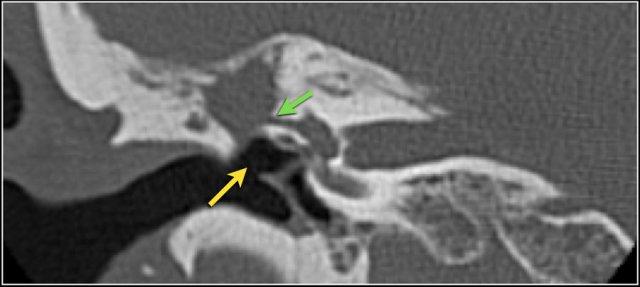

Hình ảnh một bệnh nhân có cholesteatoma.

Có một khối mô mềm ở vùng thượng nhĩ.

Lưu ý hình ảnh thủng màng nhĩ (mũi tên vàng) và bào mòn ống bán khuyên ngoài (mũi tên đỏ).

Scutum bị tù mòn.